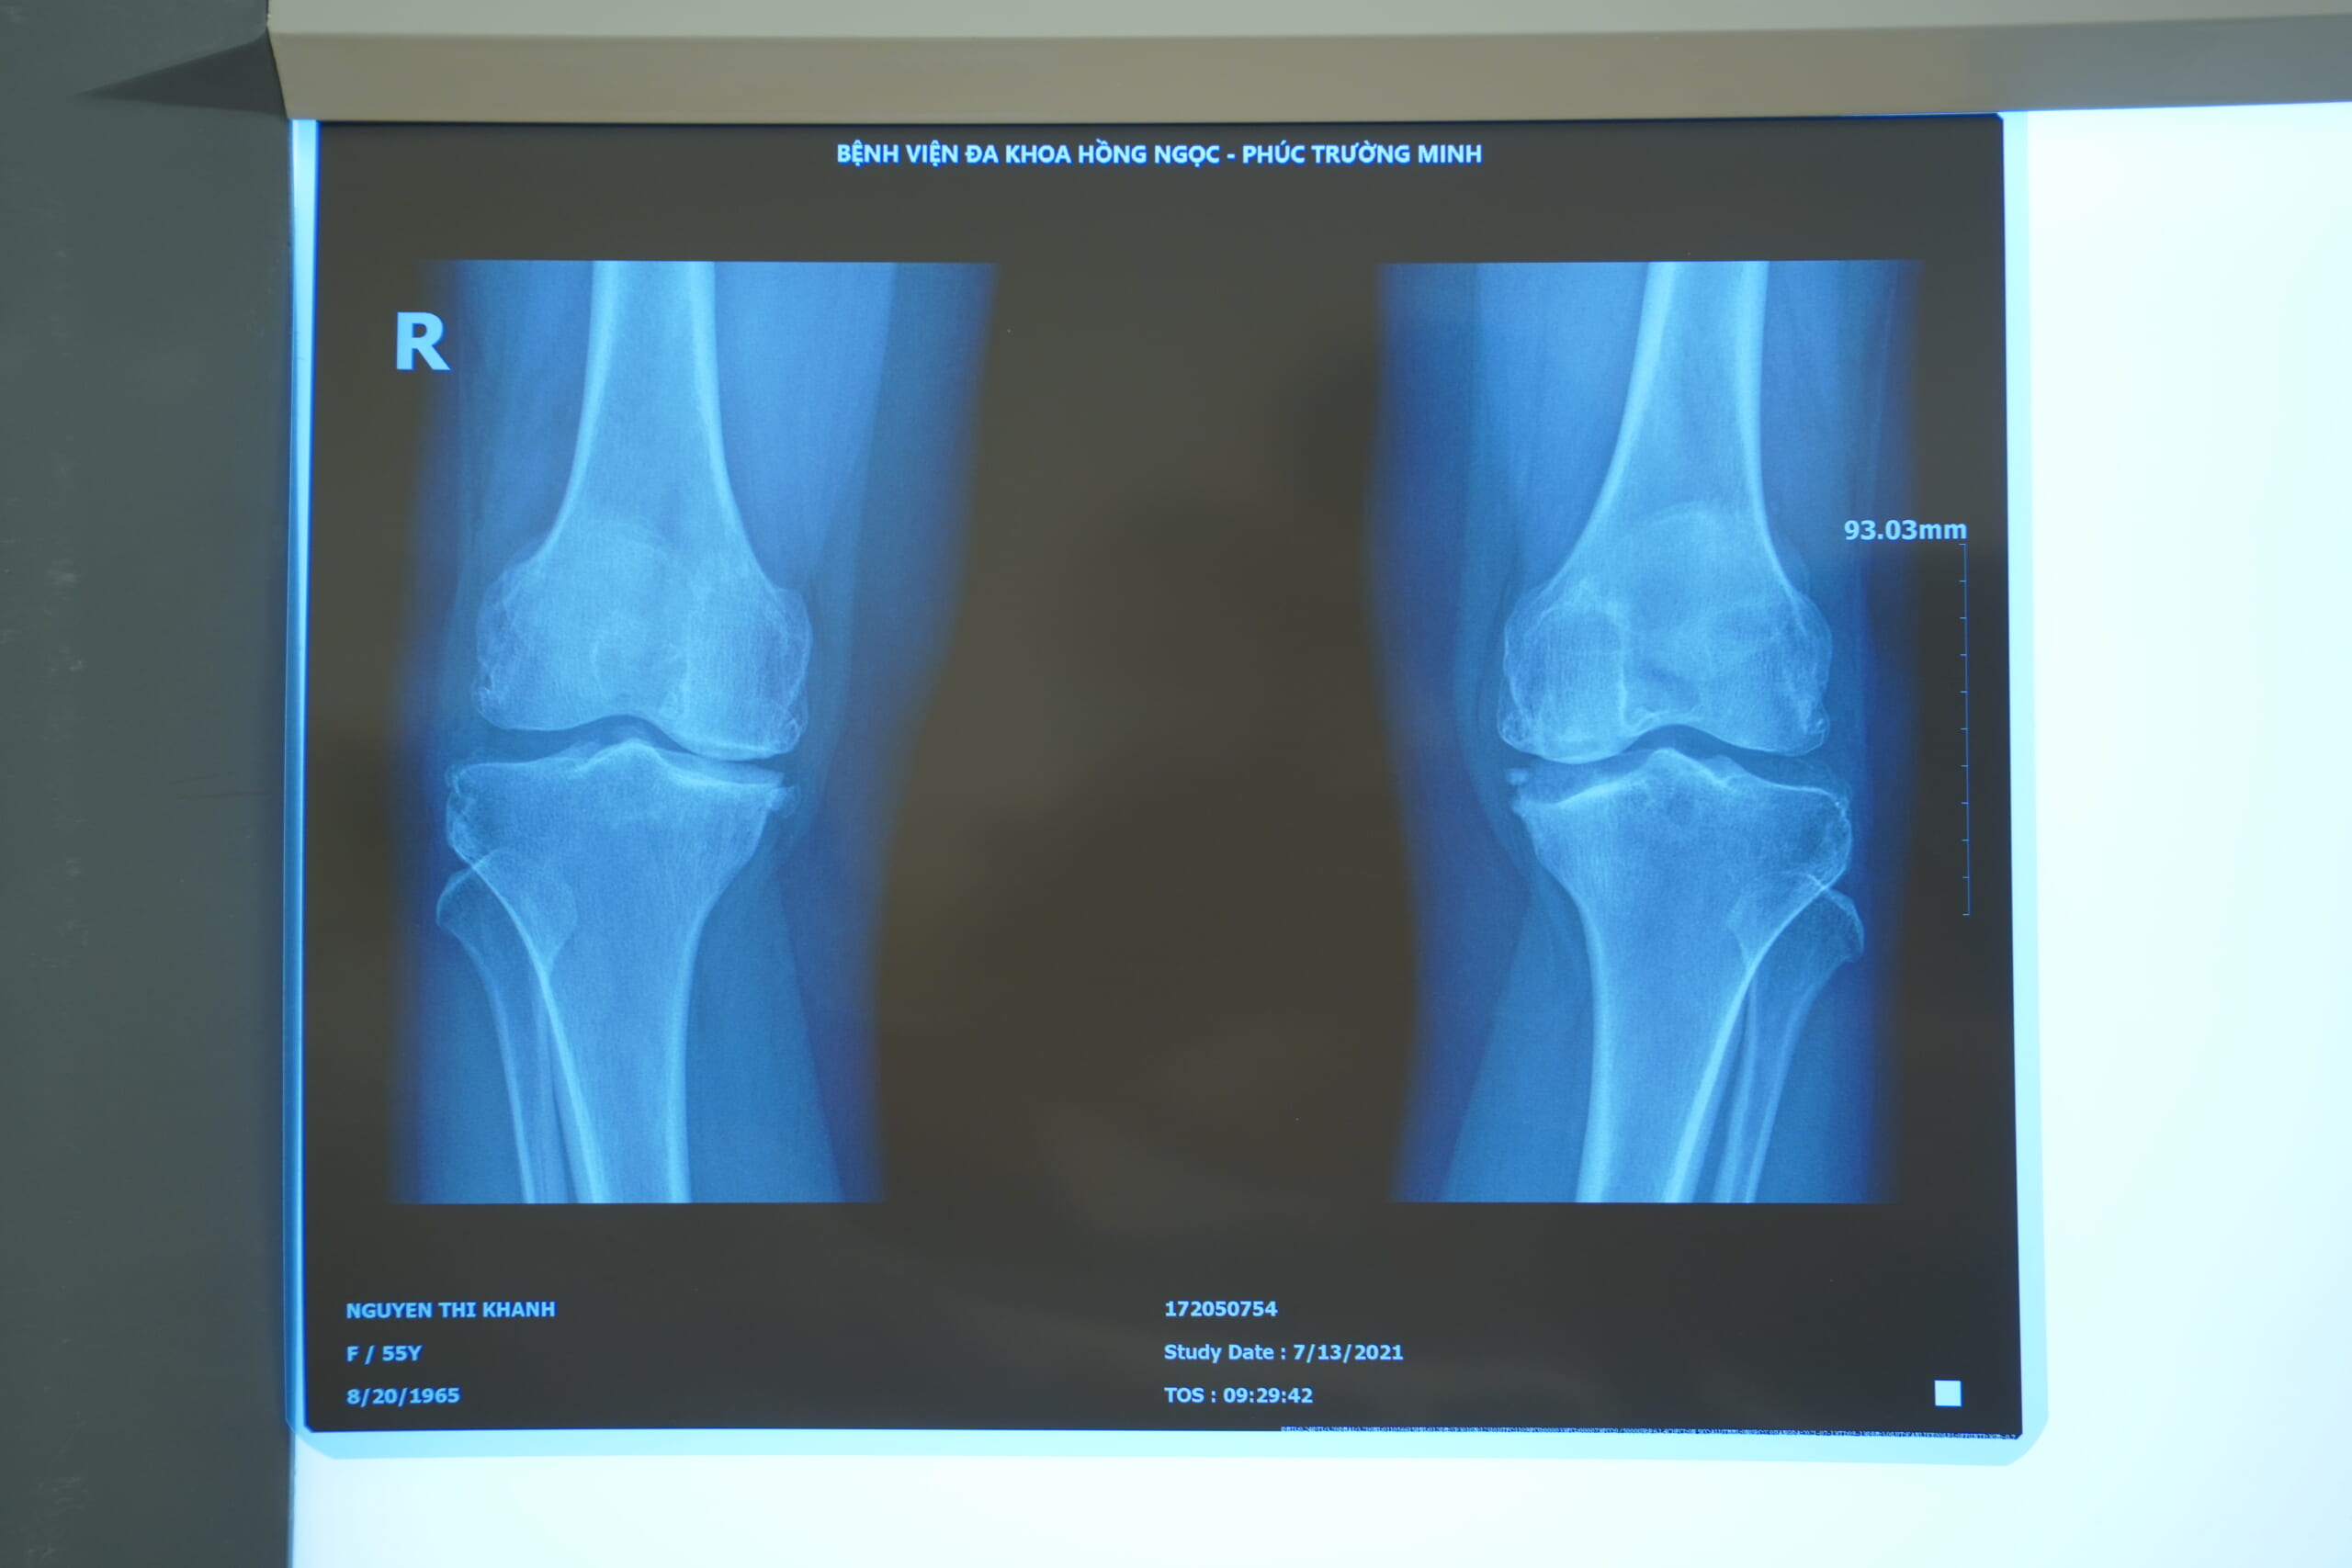

Bác sĩ Giang Lam - người trực tiếp thăm khám cho bà Khanh, đã phân tích kĩ tình trạng của bệnh như sau: “Mặt 2 xương khớp gối của bệnh nhận là đã bị tổn thương rất nhiều. Đặc biệt là ở giữa 2 khớp gối ở cả 2 chân đã có 1 khe hở rất lớn, mặt trên trong của xương chày bị tiêu sụn và xương. Chính vì vậy mới thấy rõ hiện tượng xô lệch sai vị trí, biến dạng toàn bộ khớp gối của bệnh nhân.”

ca khớp gối Ảnh: Hình ảnh phim X-quang khớp gối (phải) bị thoái hóa và khớp gối (trái) bị thoái hóa của bệnh nhân Nguyễn Thị Khanh (55 tuổi)